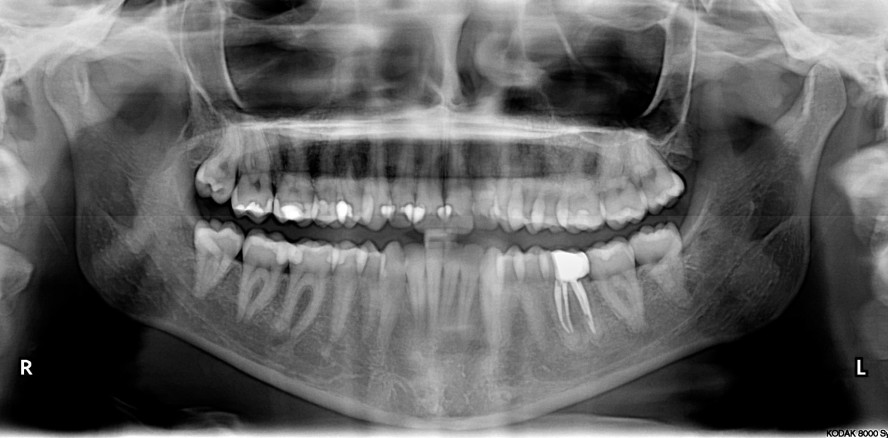

Bei konventionellen Sealern besteht häufig aufgrund der Volumenschrumpfung in der Abbindephase die Notwendigkeit, diese durch besondere Obturationstechniken auszugleichen. Bei biokeramischen Sealern kommt es zu keiner Schrumpfung, sondern tendenziell sogar zu einer geringen Expansion. Sie sind dimensionsstabil. Biokeramische Sealer wie z. B. KometBioSeal unterstützen außerdem trotz möglicher initialer zytotoxischer Wirkung das Attachment und Wachstum von Zellen und fördern die Osteoblasten- und Odontoblasten- Differenzierung. Zudem können sie das Level von Entzündungsmediatoren senken. Studien1–4 konnten sogar zeigen, dass sie einen antimikrobiellen Effekt sowohl auf Keime und Biofilme (Enterococcus faecalis) als auch Multispezies-Biofilme zeigen. KometBioSeal erfüllt außerdem die ISO-Anforderung von mehr als 3 mm Aluminium-Röntgenopazität. So lässt sich die Qualität der Obturation sehr gut evaluieren.